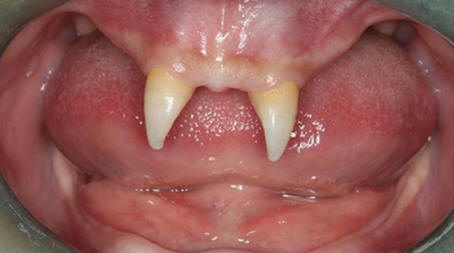

3. Najstnik je zrasel svoje vampirske zobe

Fotografija iz odprtih virov

Kitajcu je zrasel dva zelo ostra sprednja zoba zaradi česar je videti kot vampir. Decembra 2012 mati Wang Hui je sina Wang Penfei odpeljala v lokal bolnišnica za pregled. Chongqing Municipal Boy After rojstvo zelo slabo raste in v njegovih ustih sta se pojavila dva ostra fang.

Wang Hui je poskušal ugotoviti razlog za pojav tega sina nenormalne formacije in obiskali nešteto zdravniki, a ni prineslo veliko uspeha. Zdravniki iz V jugozahodni bolnišnici pravijo, da je mogoče storiti sina operacijo šele, ko postane odrasla oseba.

Stroški te operacije se lahko gibljejo od 70.000 do 80.000 RMB, to je približno 15.000 dolarjev. Po Wang Huiu postaja njen sin vedno bolj umaknjena in se pogosto spopada s sošolci, ki šepetajo o njem ali ga gledajo radovedno.